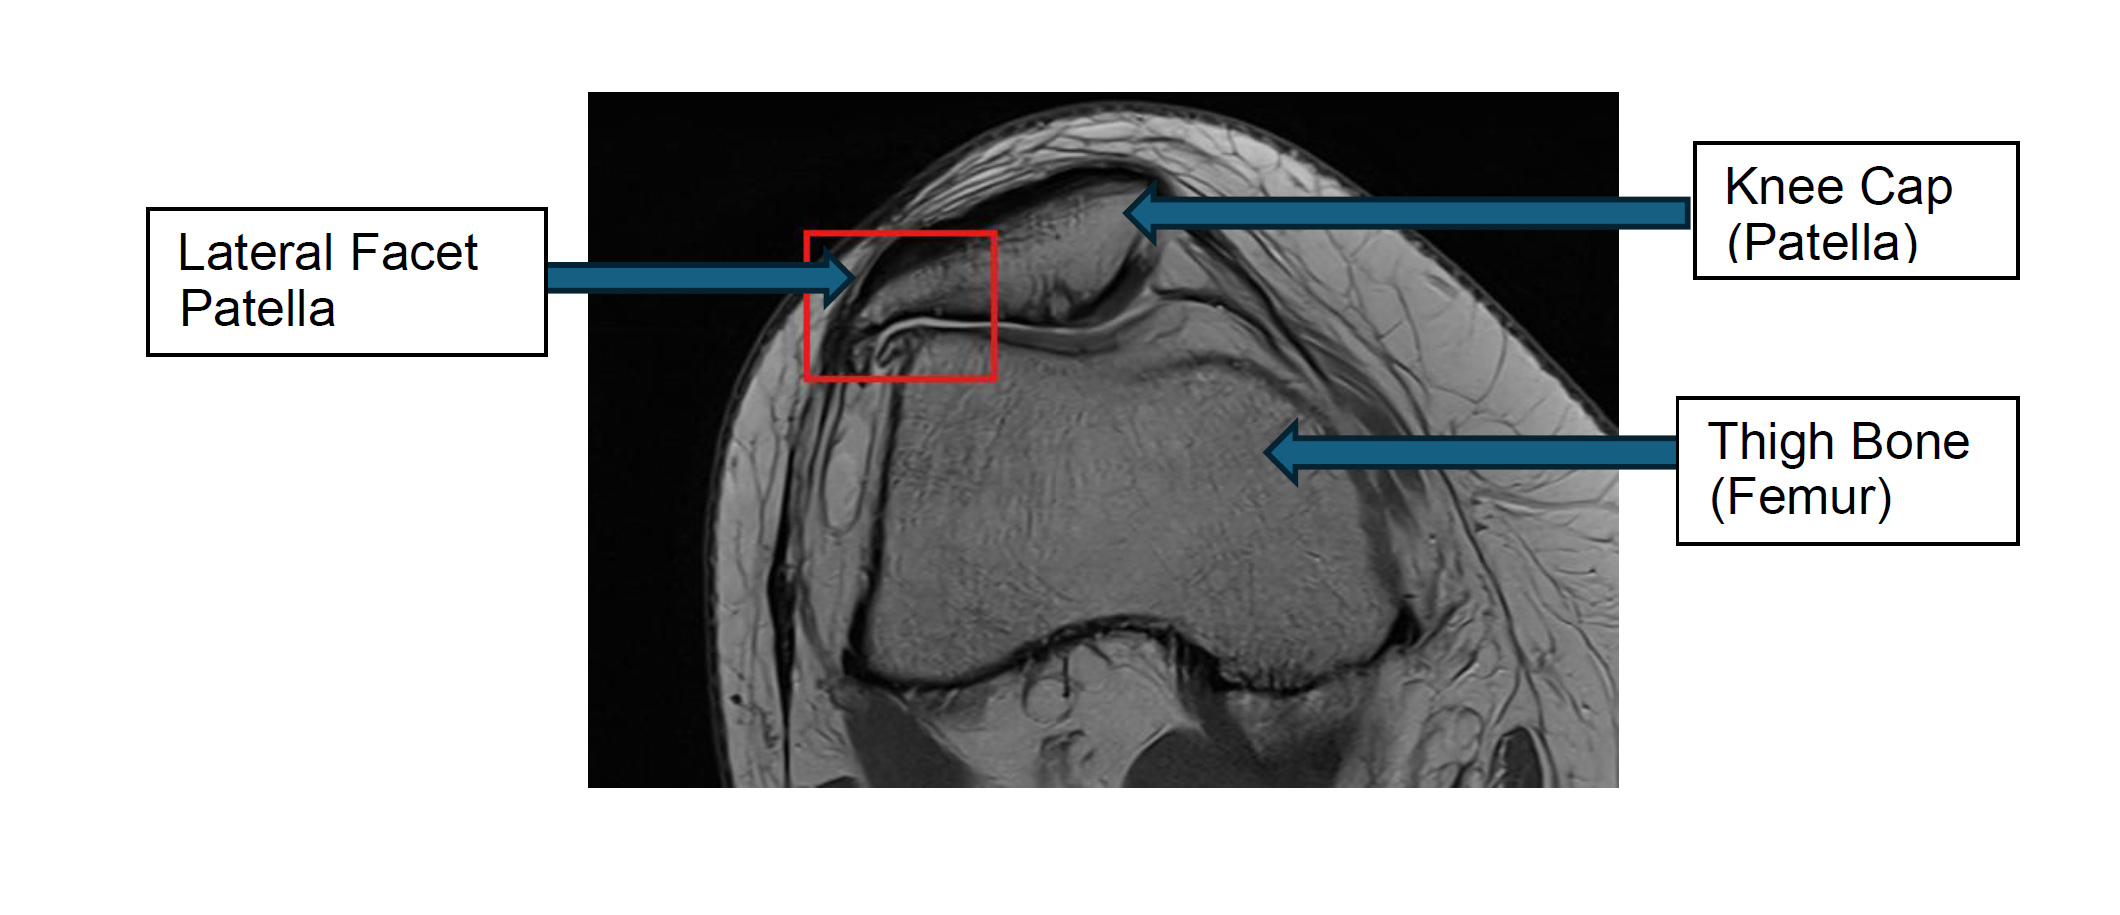

A lateral patella facetectomy is a surgical procedure used to treat pain and arthritis in the kneecap (patella), particularly when the outer (lateral) facet of the patella is worn or damaged. In this operation, the surgeon carefully removes part of the outer edge of the kneecap to reduce pressure, improve movement, and relieve pain.

What is a lateral patella facetectomy?